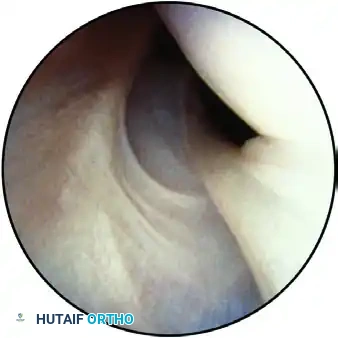

Step 2: The Anterior Compartment and Anatomical Variants

As the arthroscope is advanced anteriorly, the superior and inferior surfaces of the biceps tendon, the biceps anchor, and the superior labrum are meticulously evaluated for fraying or partial tearing.

The bicipital arch, formed by the superior glenohumeral ligament (SGHL) and the coracohumeral ligament (CHL), is inspected to ensure the biceps tendon is stable and properly centered.

View of the anterior structures: The superior glenohumeral ligament and subscapularis tendon are visible on the right, with the middle glenohumeral ligament located inferiorly.

If a SLAP lesion is suspected, it must be dynamically probed to determine stability. These lesions typically result from traction injuries (e.g., overhead throwing) or a fall on an outstretched extremity, causing superior translation of the humerus against the biceps-labral complex.

The arthroscope is then directed over the anterior labrum toward the anterior "soft spot"—a triangular interval bounded by the biceps tendon proximally, the subscapularis tendon distally, and the glenoid articular surface inferiorly.